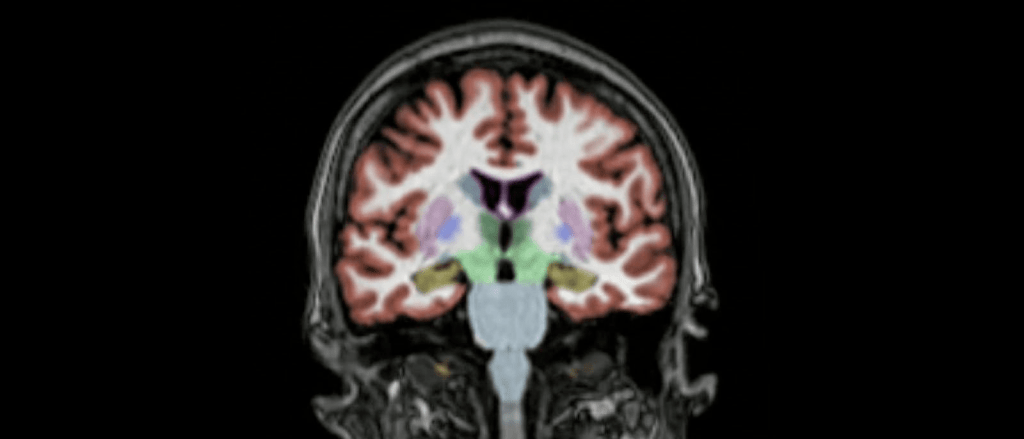

Image credit: Columbia University Irving Medical Center Newsroom